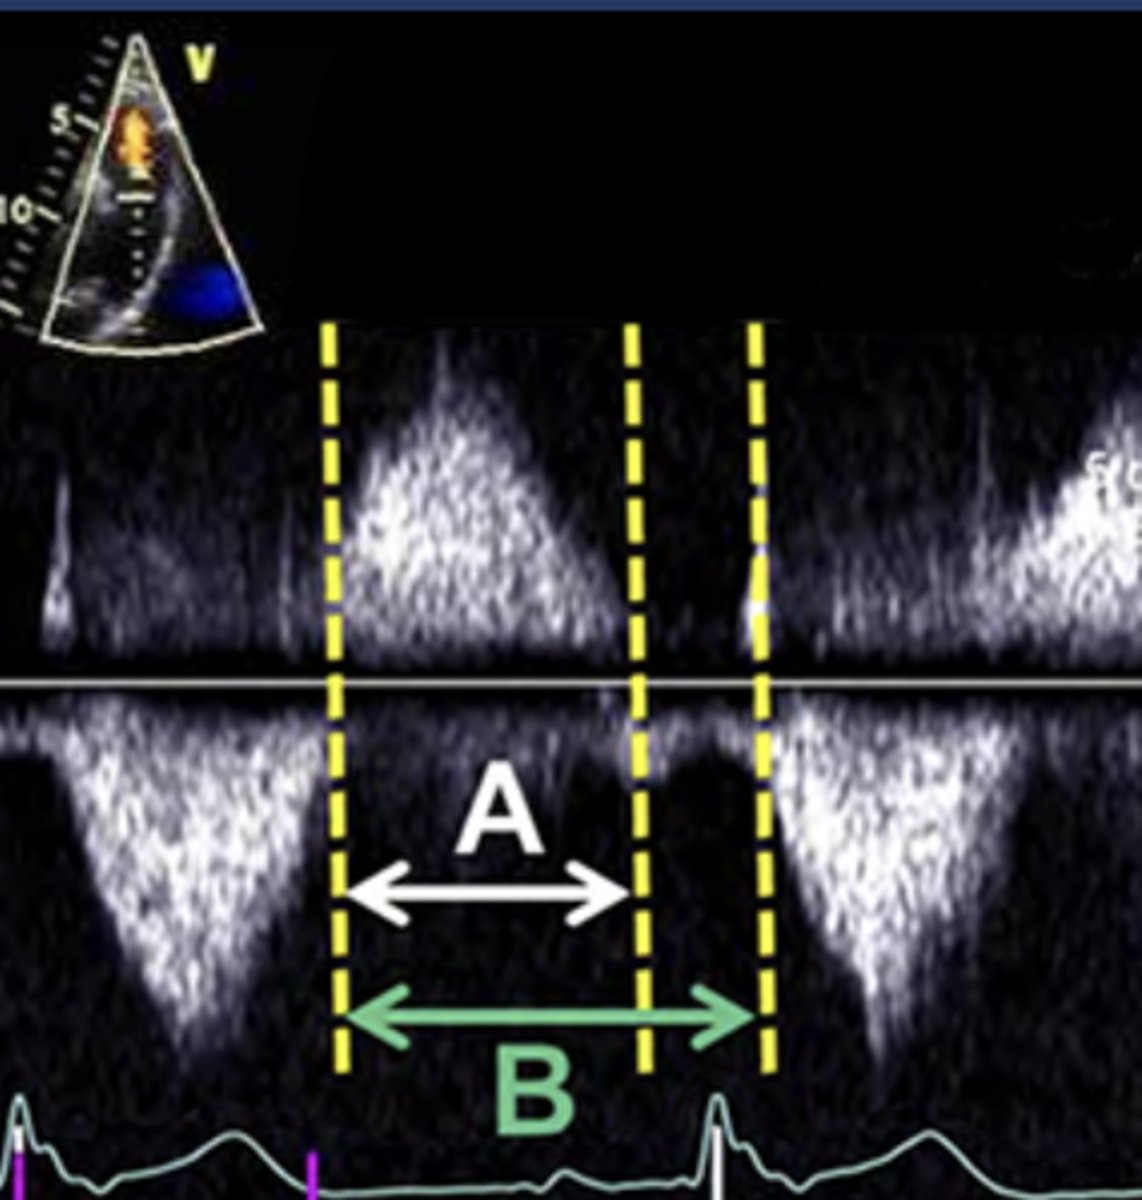

PR Index

Ratio of PR duration to total diastolic duration

PR Index for Severe PR

< 0.77